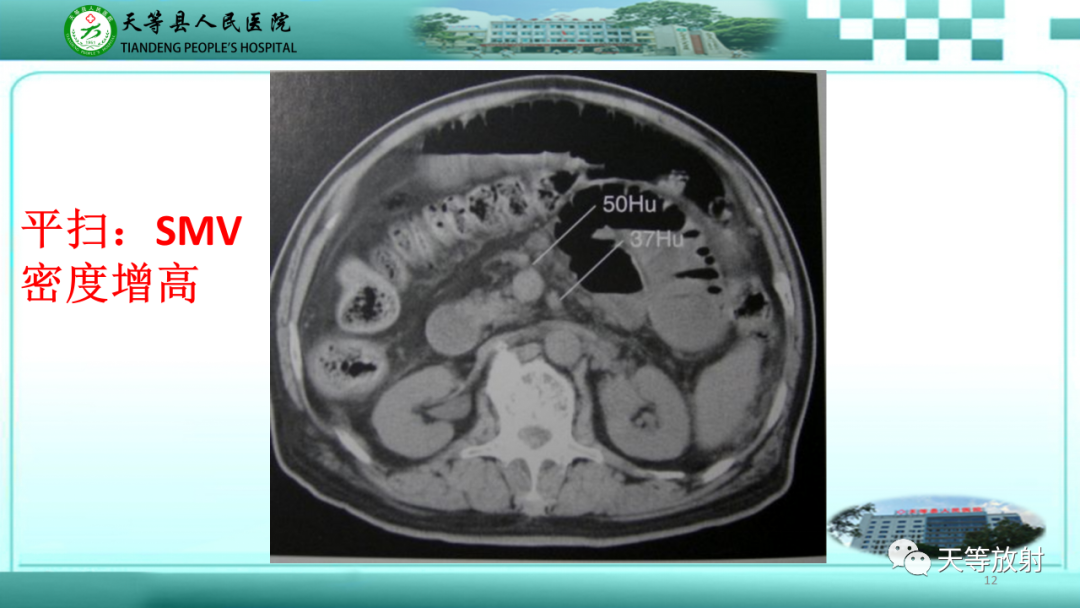

【PPT】缺血性肠病的影像学表现-12